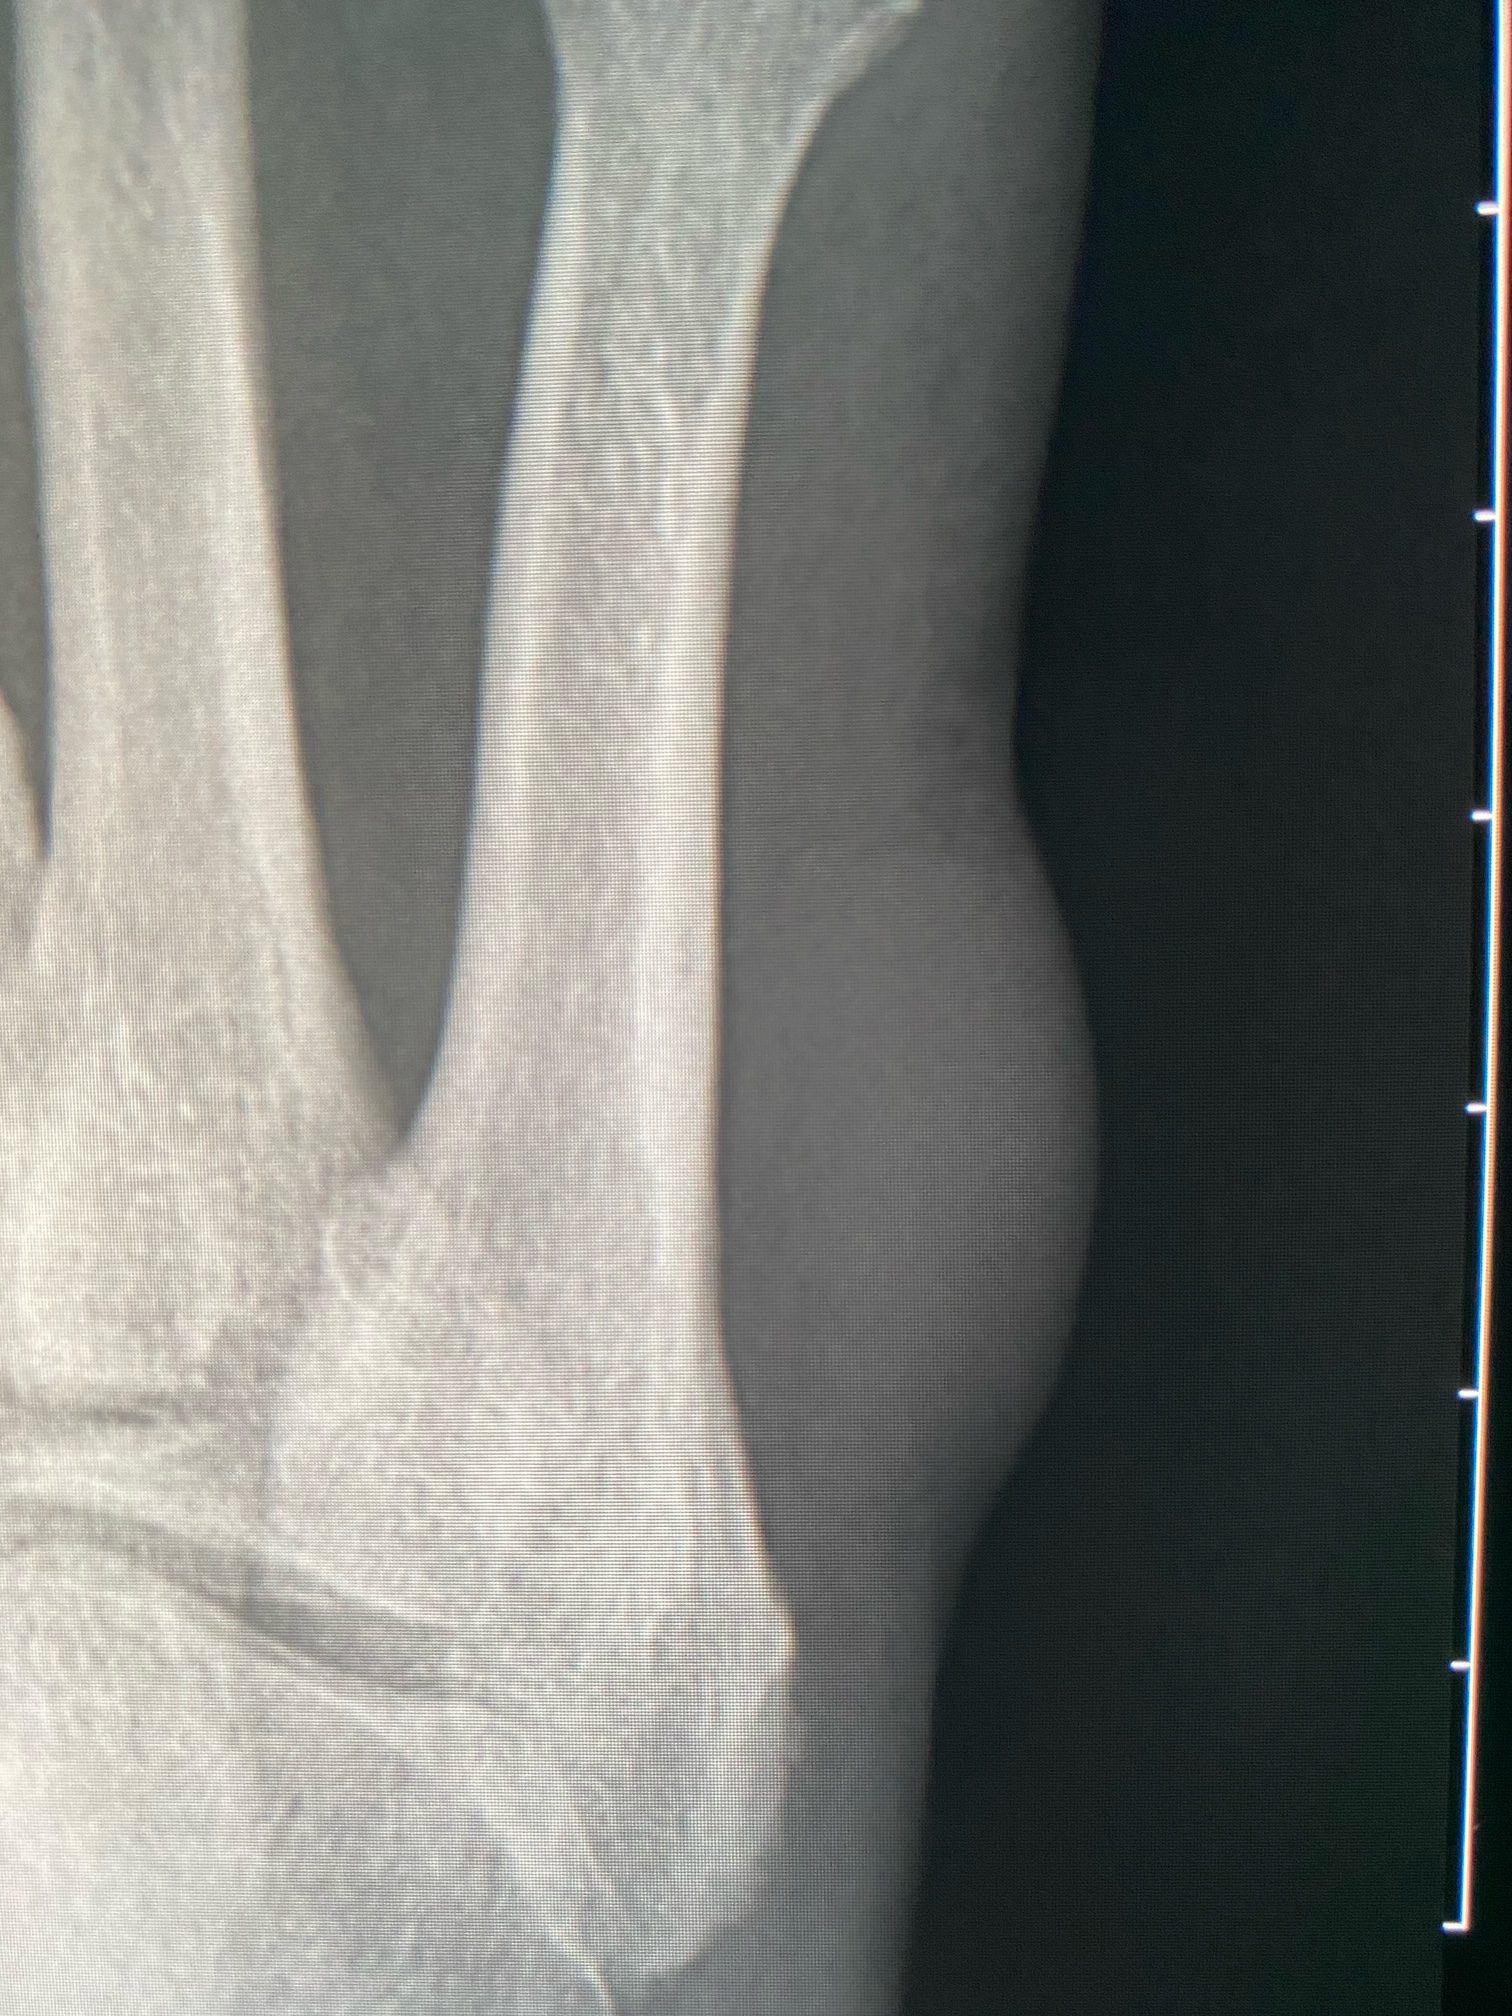

First I’ve seen it but there are plain films going back to 2008 where it looks similar in size and then has slowly calcified with central dystrophic calcification—showing 2008, 2011, 2018, 2020 (looking scarily like bone matrix):

I’m reading an MR today. The soft tissue component surrounding the calcification is T2 bright, T1 iso to muscle, no diffusion restriction, with avid homogenous enhancement:

It appears to be subdermal centered in the subq fat and I don’t see any efferent or afferent vessels.

The patient finally had this resected and path came back as a “calcified angioleiomyoma.”